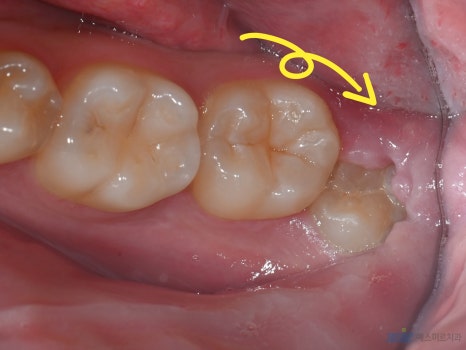

왼쪽 아래 음식물이 끼고, 양치관리가 안되어 잇몸이 붓고 통증이 생겨서 발치하는 경우